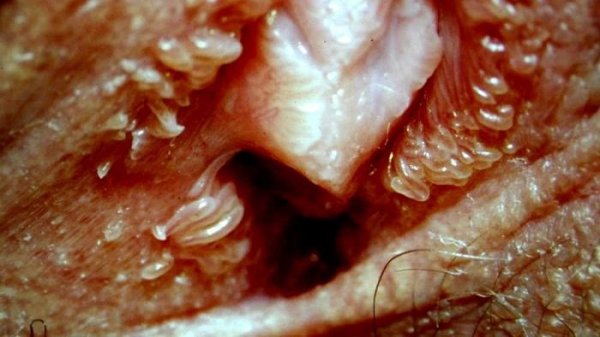

ظاهر این برجستگیها معمولاً به صورت پاپولهای کوچک، نرم، همرنگ پوست یا کمی صورتیرنگ است. این ضایعات معمولاً در ردیفهای منظم در اطراف دهانه واژن قرار دارند و اندازه آنها بین یک تا دو میلیمتر است. وستیبولار پاپیلوماتوز بدون درد، بدون خارش و بدون ترشح است و بههیچوجه مسری نیست.

یکی از نکات مهم در تشخیص این عارضه، افتراق آن از بیماریهایی مانند زگیل تناسلی یا عفونتهای پوستی است. تفاوتها عبارتند از: عکس وستیبولار پاپیلوماتوز در مردان